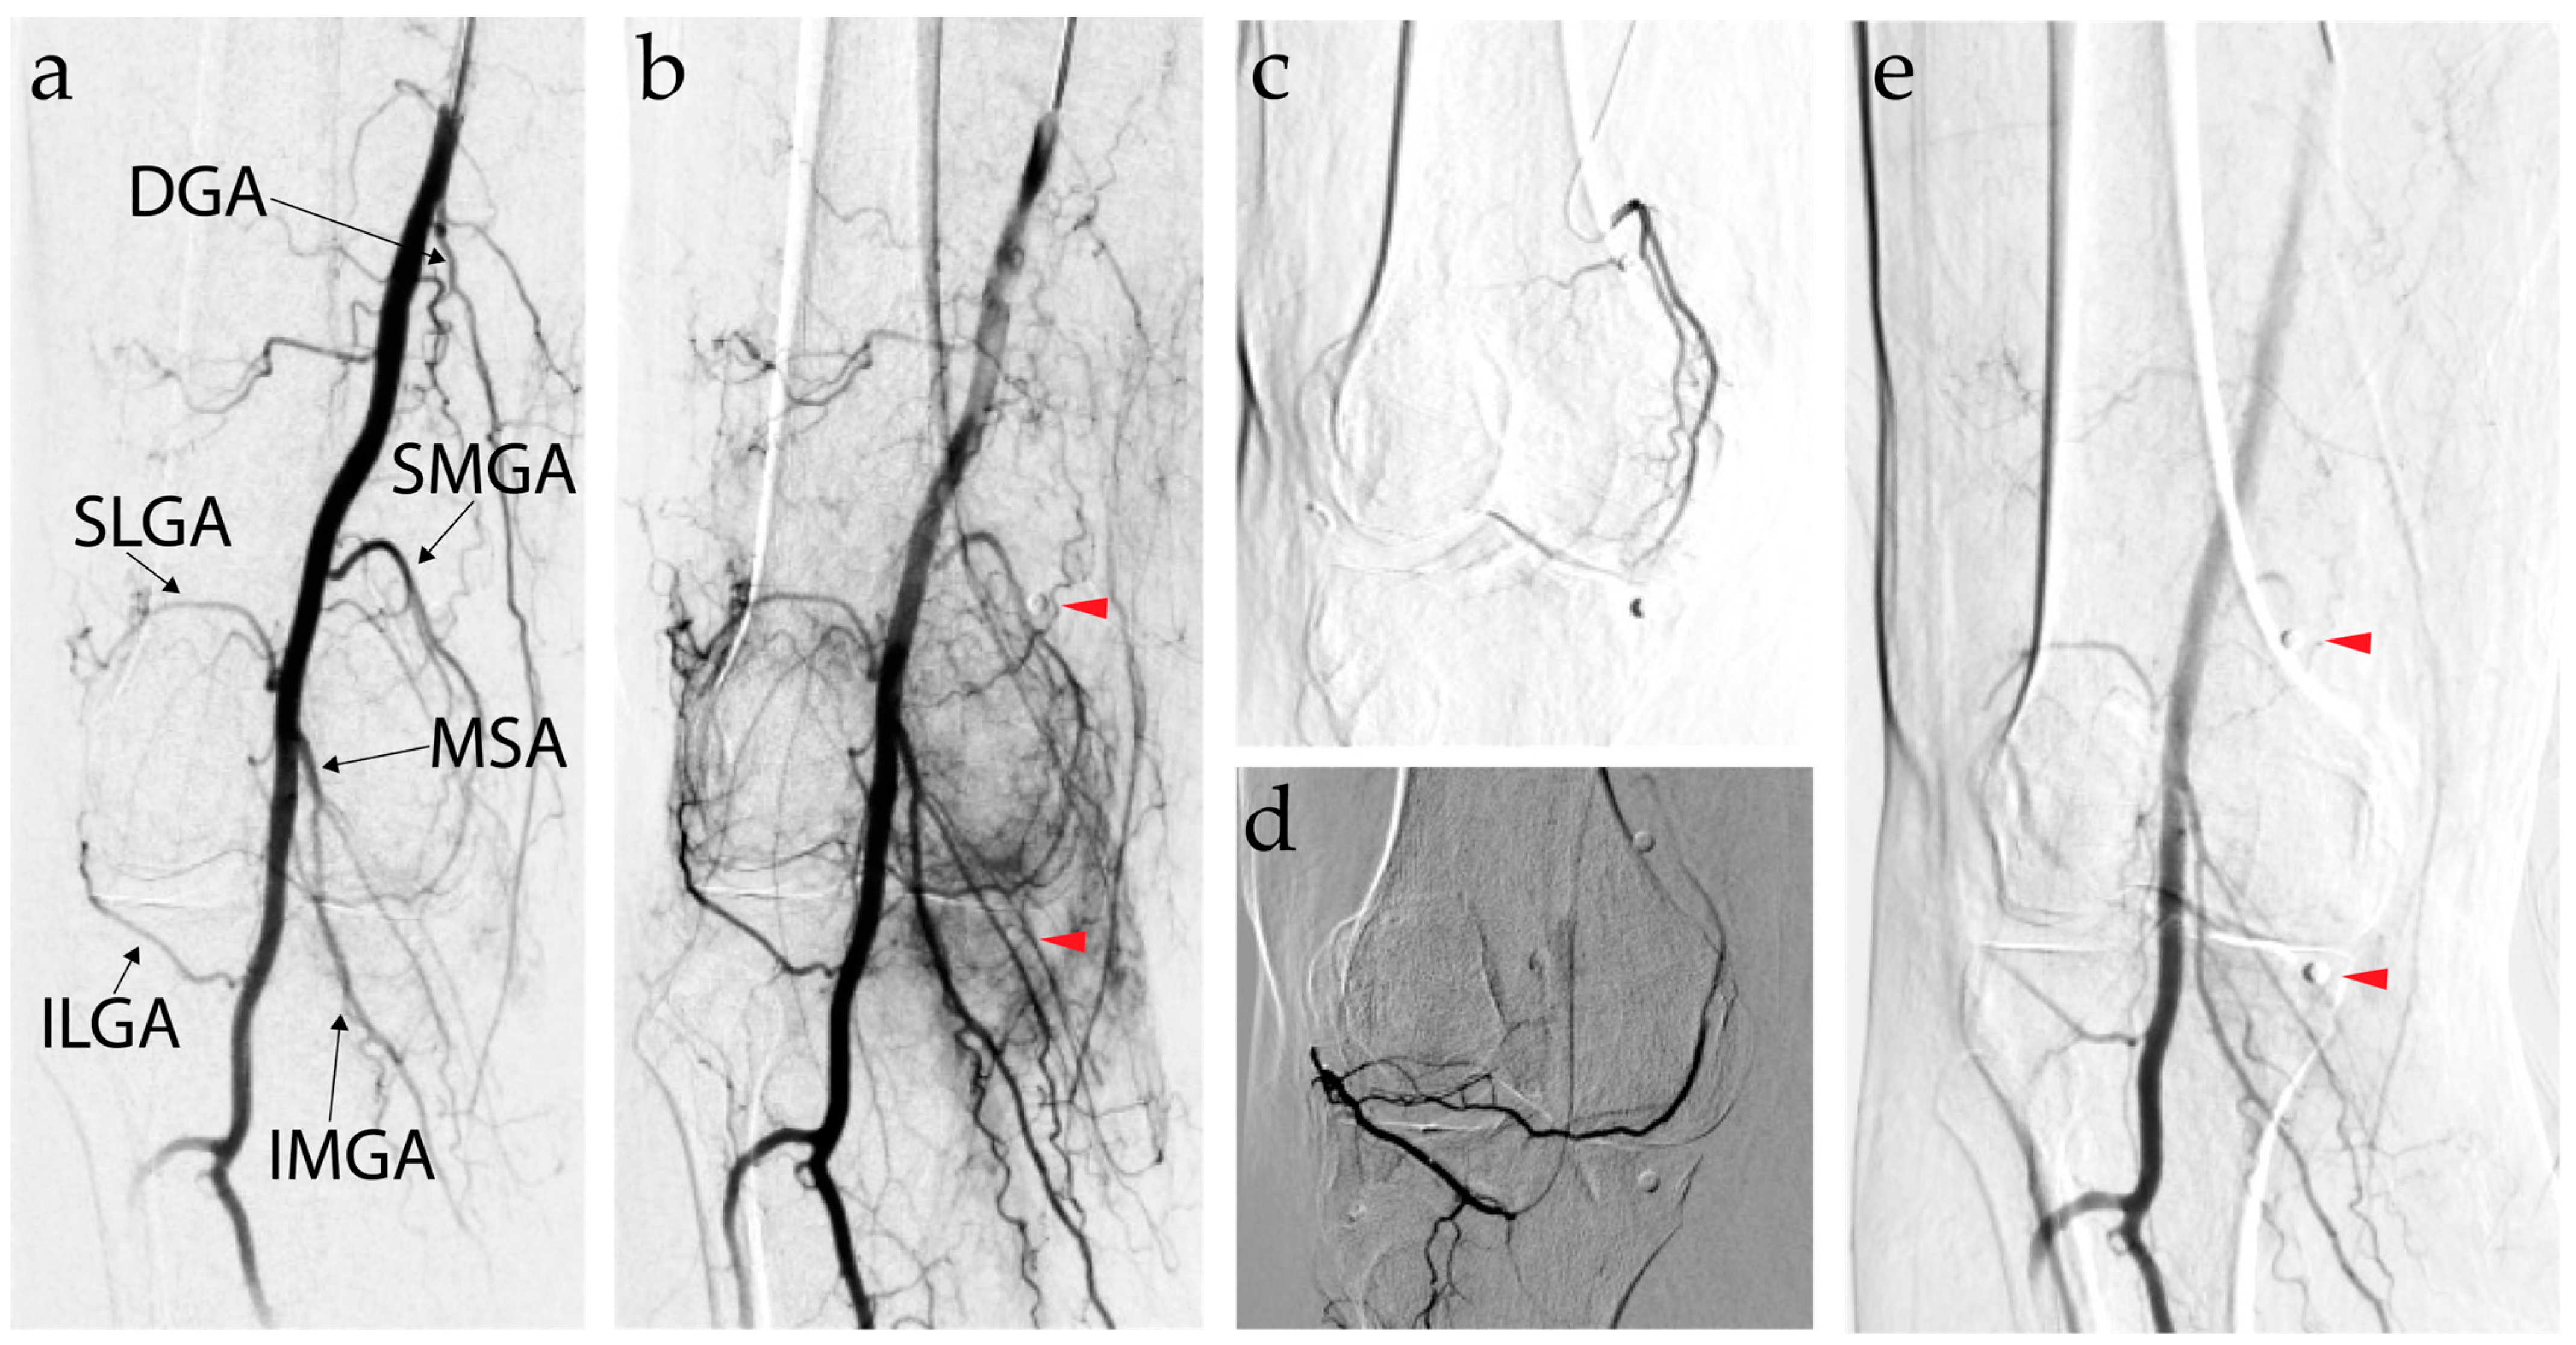

7.3. Genicular Artery Embolization Technique

7.1. Background and Mechanism of Action of Genicular Artery Embolization